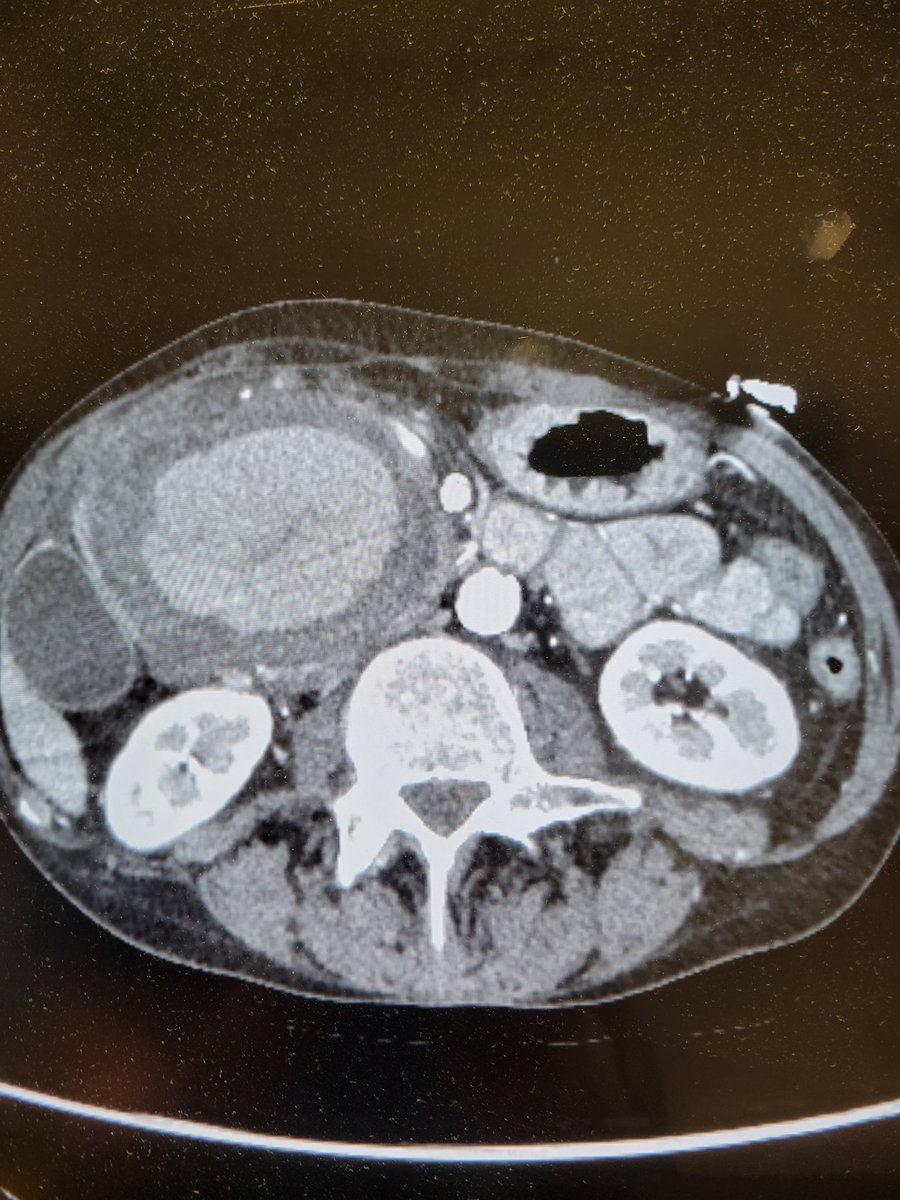

Great case and amazing job #irad #interventionalradiology

Patient presents with abdominal pain and distention found to have an enormous GDA pseudoaneurysm. Emergently taken to IR and coil embolization performed by Dr. Niman. The size is just unbelievable! @TempleRadRes @SIRRFS @SIR_ECS @SIRspecialists #IRAD